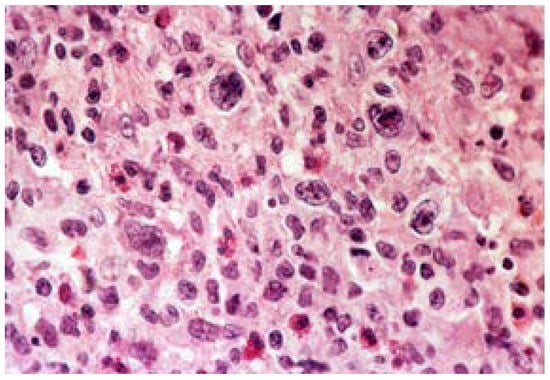

- Deterioration of the mucosa and the entire gastric wall, caused by necrosis, that can progress to the serous membrane, thus generating perforation of the stomach;

- An inflammatory lymphoplasmacytic process at the bottom of the ulcer and its margins;

- Microvascular changes in the ulcer’s perimeter with arteriole hyalinosis.